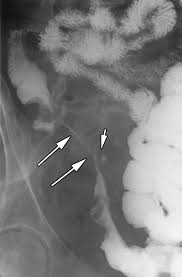

loss of haustra looks like what on imaging

lead pipe sign

UC

lead pipe sign, UC

string sign, CD